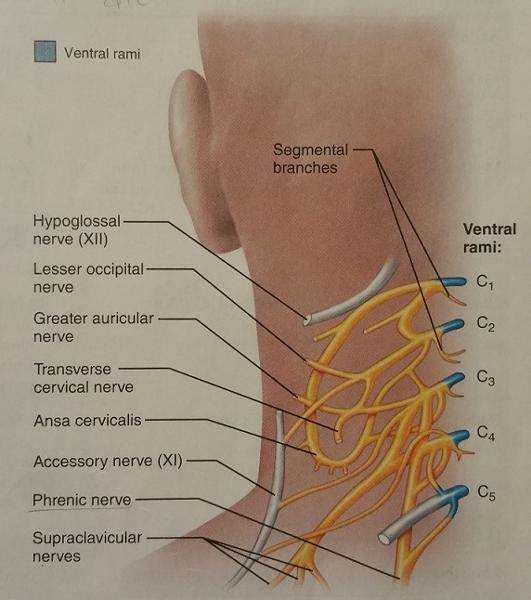

The cervical plexus arises from the ventral rami of what cervical nerves?

C1-C5

The cervical plexus supplies muscles of which 2 body parts?

1. Shoulder

2. Neck

What is the major motor branch (nerve) of the cervical plexus?

Phrenic nerve

The phrenic nerve arises from the ventral rami of which cervical nerves?

C3-C5

The phrenic nerve innervates which body part?

Diaphragm

What is the primary danger of a broken neck (in regard to which nerve being damaged)?

The phrenic nerve may be severed

If the phrenic nerve is severed, what 2 dangerous conditions could occur?

1. Paralysis of the diaphragm

2. Cessation of breathing